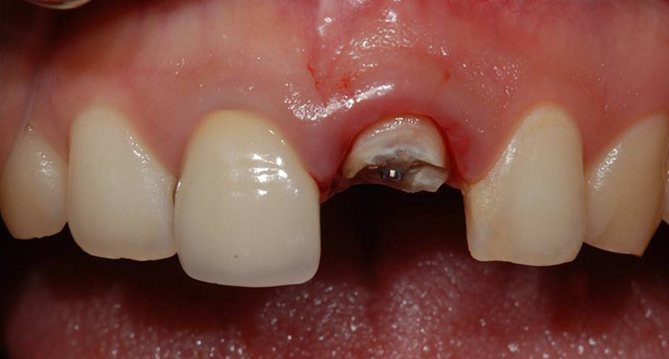

임플란트

환자만을 생각한

임플란트, 1:1맞춤 지대주

사용하여 진료

TOP-DOWN TREATMENT,

임플란트 시술 전 보철과 전문의의 구강평가시스템

환자의 교합, 치아 상실 부위, 치주상태 등을 평가한 후 보철의 치료계획을

먼저 세우고 임플란트 수술 계획을 세우는 것을 말합니다.

임플란트는 구강내 질환이 있거나 잇몸이 약한 등 구강환경에 따라 제약이 따르기 때문에

연세새빛치과에서는 보철과 전문의의 구강 평가 후 임플란트 시술 가능여부를 체크합니다.

내 상태에

맞는 지대주 사용

맞춤 지대주 사용으로

내 구강상태와 맞는 임플란트

연세새빛치과 상악동거상임플란트 사례

연세새빛치과 전악 임플란트 사례